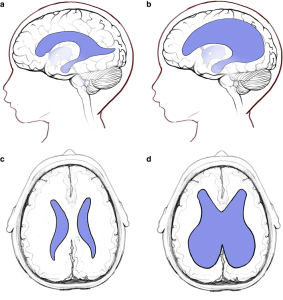

Giãn não thất thai nhi là gì? Định nghĩa: Giãn não thất là tình trạng [...]

GIÃN NÃO THẤT LÀ GÌ: NHỮNG ĐIỀU CẦN BIẾT ĐỂ CHA MẸ KHÔNG QUÁ LO LẮNG

Khi đi siêu âm thai định kỳ, nhiều phụ huynh không khỏi lo lắng khi [...]